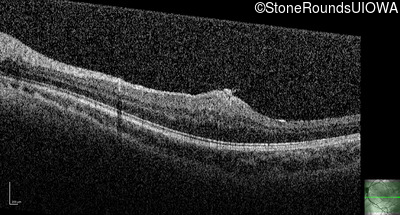

This 9 year old male was noted to have some crossing of his eyes at 2 months of age and the eye exam which followed identified a retinal lesion in the right eye. When he was six years old an epiretinal membrane was noted in his left eye. Two years later it was decided that it was a thin hamartoma in that eye as well. He underwent neuroimaging at age 7 which identified bilateral acoustic neuromas.

| Age at visit: 8 years |

| Age at visit: 10 years |

| Age at visit: 11 years |

| Age at visit: 14 years |